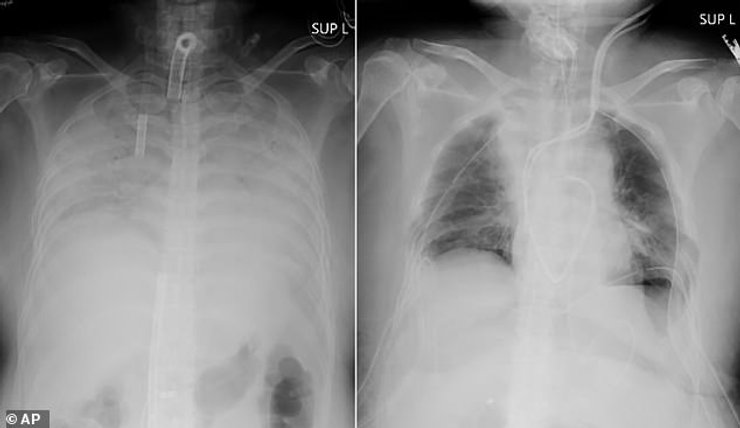

рентген, снимок, поражение, легкие

Рентгеновский снимок показал масштабы поражения легких пациентки